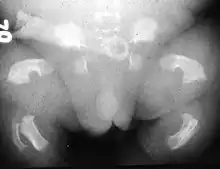

Radiogram of a baby born with thanatophoric dwarfism

Thanatophoric dysplasia is a severe skeletal disorder characterized by a disproportionately small ribcage, extremely short limbs and folds of extra skin on the arms and legs.

Infants with this condition have disproportionately short arms and legs with extra folds of skin. Other signs of the disorder include a narrow chest, small ribs, underdeveloped lungs, and an enlarged head with a large forehead and prominent, wide-spaced eyes. Thanatophoric dysplasia is a lethal skeletal dysplasia divided into two subtypes. Type I is characterized by extreme rhizomelia, bowed long bones, narrow thorax, a relatively large head, normal trunk length and absent cloverleaf skull. The spine shows platyspondyly, the cranium has a short base, and, frequently, the foramen magnum is decreased in size. The forehead is prominent, and hypertelorism and a saddle nose may be present. Hands and feet are normal, but fingers are short. Type II is characterized by short, straight long bones and cloverleaf skull.[1] It presents with typical telephone-handle shaped long bones and H-shaped vertebrae.

Infants with type 1 thanatophoric dysplasia also have curved thigh bones, flattened bones of the spine (platyspondyly) and shortened thoracic ribs. Note: Prenatal ultra-sound images of the ribs sometimes appear asymmetrical when in fact they are not. In certain cases, this has caused a misdiagnosis of osteogenisis imperfecta (OI) type II.